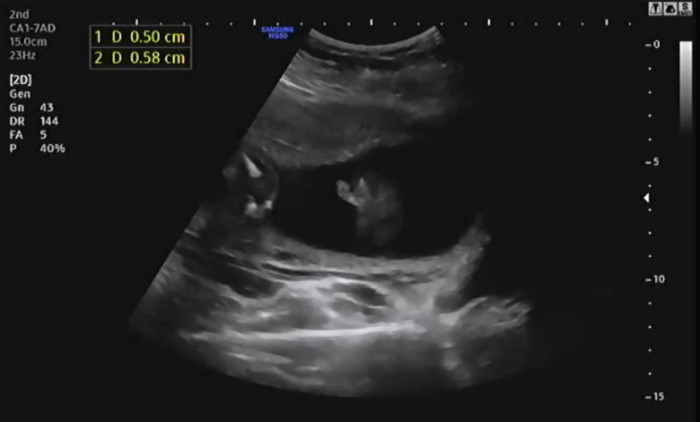

태아의 옆모습을 보며 콧대를 확인한다. 코뼈 길이를 측정하는데 엄마를 닮았는지 코뼈 길이가 짧아 의사가 두 번이나 측정해서 겨우 0.58cm임을 확인했다. 코뼈 길이를 측정할 때 무안해서 남편이랑 눈을 마주치자마자 슬며시 웃었다.